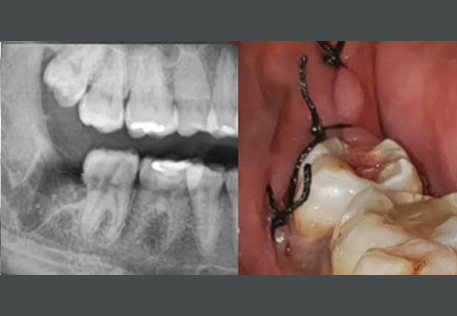

Comprehensive oral examination with digital X-rays to assess the position and condition of your wisdom teeth.

1. Impaction – When the wisdom tooth does not have enough space to emerge properly, it may become trapped in the gums or jawbone.

2. Infection – Bacteria can accumulate around a partially erupted wisdom tooth, leading to pericoronitis (gum infection).